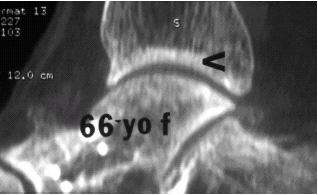

>К нам обратился пациент 73 лет с жалобами на боли и деформацию в

> области левого голеностопного сустава.

> В анамнезе: в 1980 году перелом обеих лодыжек с вывихом стопы кнаружи.

> Лечился консервативно: одномоментная репозиция переломовывиха в левом

> голеностопном суставе с трансартикулярной фиксацией голеностопного

> сустава спицами Киршнера через пяточную, таранную, большеберцовую

> кости. Накладывалась гипсовая иммобилизация. Даная манипуляция

> осложнилась нагноением с развитием гнойного артрита. Были удалены

> спицы, сустав со слов больного, промывался растворами, но не

> вскрывался, получал антибиотики.

>

> Гнойный процесс был купирован, и рецидива с тех пор не было. Об-но:

> Левый голеностопный сустав деформирован за счет разрастания костной

> ткани и отечности мягких тканей. Левая стопа с вальгусной установкой,

> практически отсутствуют все своды левой стопы (стопа плоская). Полный

> объем движений в левом голеностопном суставе максимум достигает 15 гр,

> движения стопы в основном за счет подтарнного сустава. Пальпаторно

> область голеностопного сустава не столь болезненна, как болезненна

> область подтаранного сустава и область таранно-ладьевидного сустава.

> После изучения объективного статуса, анамнеза, рентгенснимков,

> больному предложен был трехсуставной артродез, так-как мы сочли это

> наиболее приемлемым в данном случае. Но больной отказывается от данной

> операции и настаивает на эндопротезировании левого голеностопного

> сустава. Во первых, наше отделение не имеет опыта в эндопротезиовании

> голеностопного сустава. Во вторых, нам кажется, что трехсуставное

> артродезирование в данном случае наиболее подходящее. Причиной тому,

> на наш взгляд, выраженная деформация левой таранной кости, как

> следствие аваскулярного некроза, и то, что болит не голеностопный

> сустав в данном случае (хотя в нем и ограничено движение), а

> подтранный и таранно-ладьевидный суставы, и то, что эндопротезирование

> одного голеностопного сустава не решит проблем в подтаранном,

> ладьевидно-таранном сочленениях. Наши доводы оказались безуспешными, а

> так как пациент  является ученым, требовал доказательной базы наших

> умозаключений. Ваше мнение по данному случаю, и мы были бы благодарны,

> если у кого то есть материал по данной теме или есть ссылки. Заранее

> благодарны всем, кто примет участие в обсуждении данной темы.

> Batal